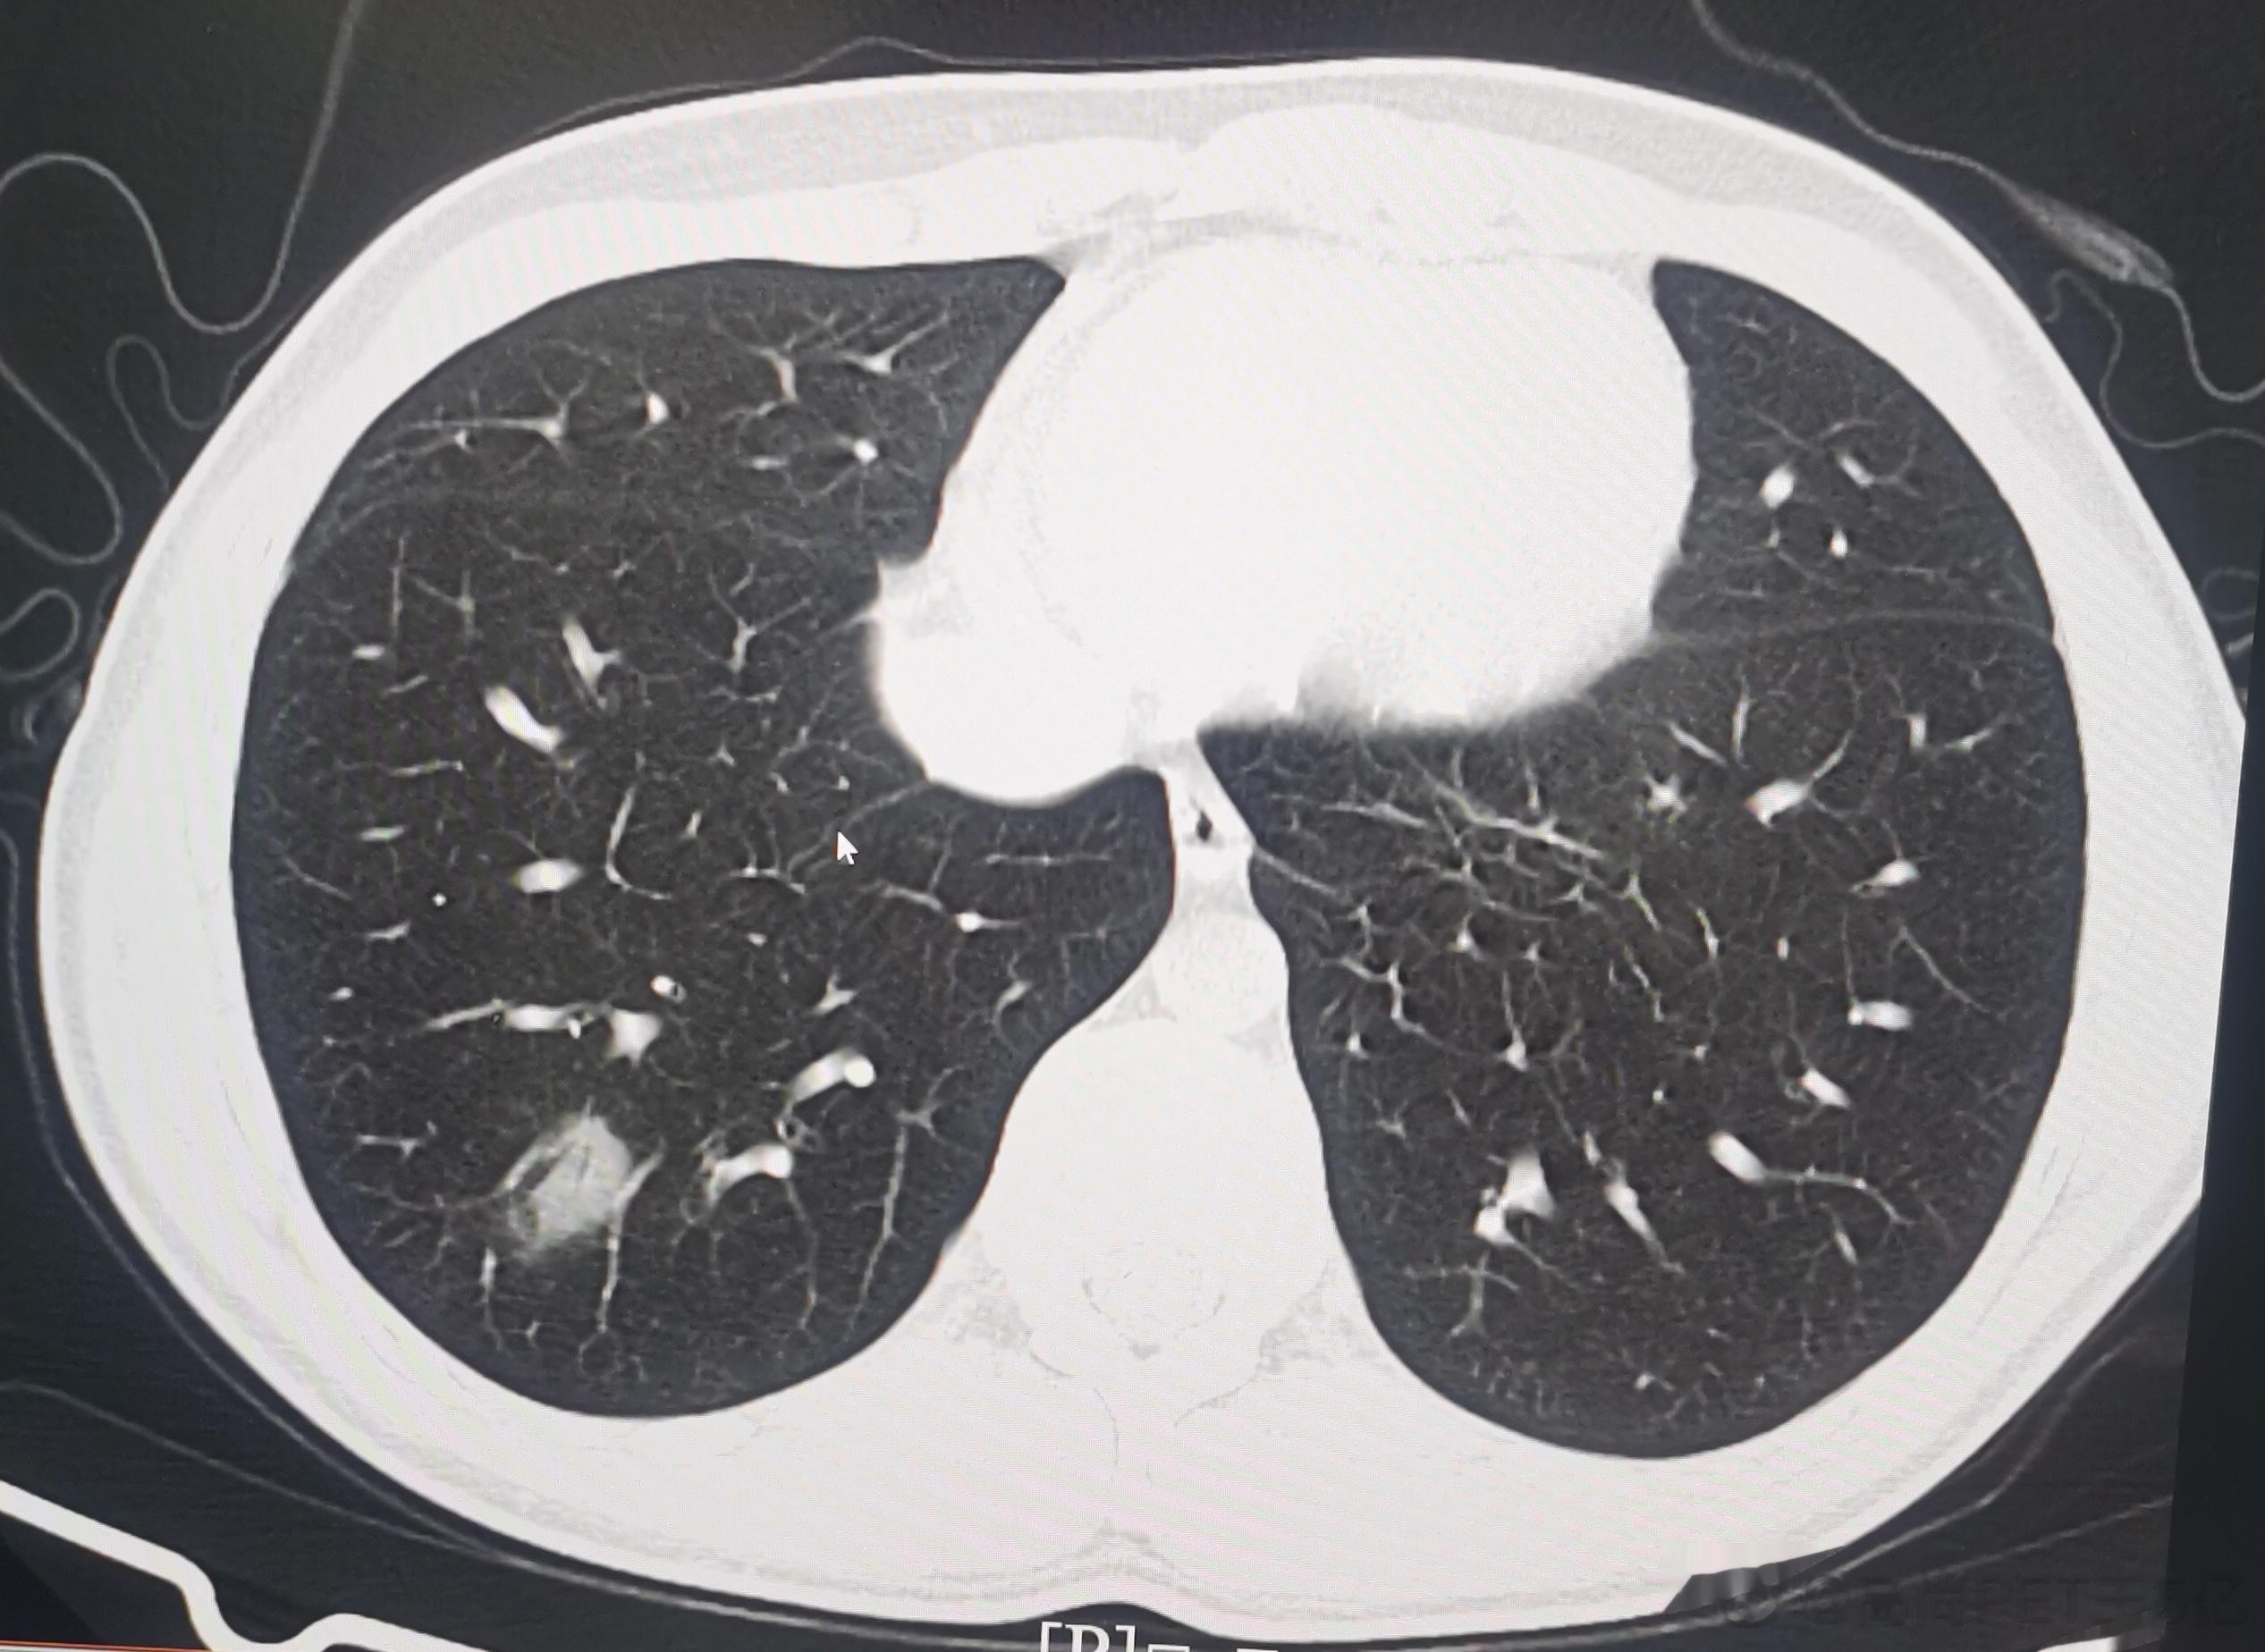

今日我们高尚影像中心新冠肺炎筛查病人是108例,其中28例有轻度新冠肺炎影像表现,检出率接近26%,最最小14岁(下面第一排CT图像),最大年龄是87岁(下面第二排CT图像),大部分人的年龄超过60例。由此可以看出,新冠病毒肺炎可能会累及各个年龄段,但主要还是60岁以上老年人群。如果新冠感染超过2周咳嗽症状还不减轻者,最好做一个胸部CT判断有无新冠病毒肺炎,这对于决策治疗方案及预测治疗效果都很关键。#老年人感染新冠后小心肺炎##感染新冠都要做CT吗#

今日我们高尚影像中心新冠肺炎筛查病人是108例,其中28例有轻度新冠肺炎影像表现,检出率接近26%,最最小14岁(下面第一排CT图像),最大年龄是87岁(下面第二排CT图像),大部分人的年龄超过60例。由此可以看出,新冠病毒肺炎可能会累及各个年龄段,但主要还是60岁以上老年人群。如果新冠感染超过2周咳嗽症状还不减轻者,最好做一个胸部CT判断有无新冠病毒肺炎,这对于决策治疗方案及预测治疗效果都很关键。#老年人感染新冠后小心肺炎##感染新冠都要做CT吗#